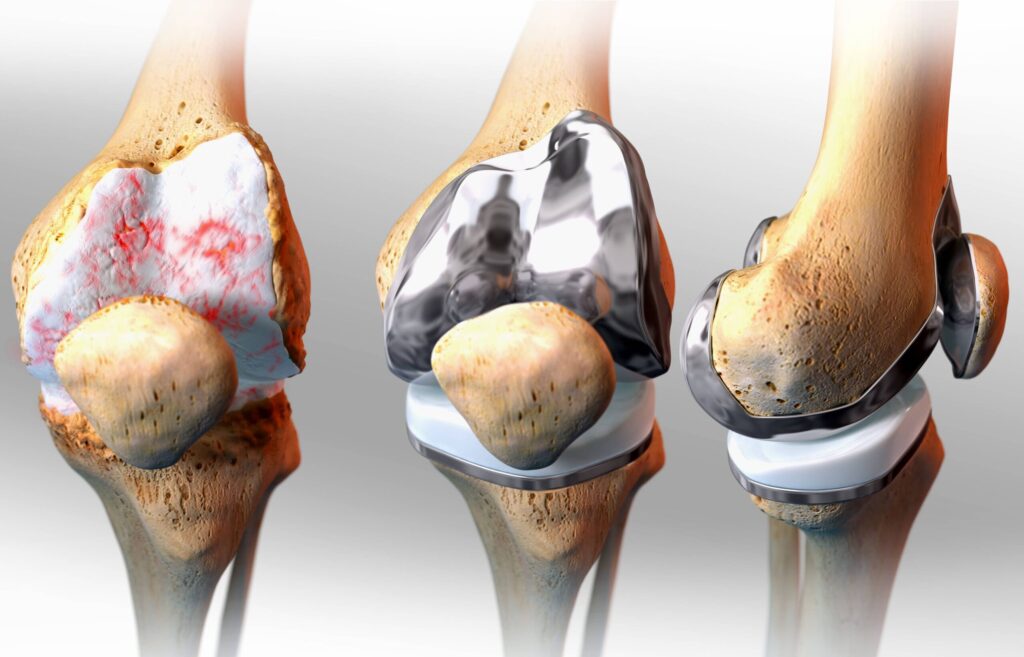

This impressive growth trajectory is primarily driven by the escalating prevalence of osteoarthritis, a challenging joint condition necessitating effective cartilage restoration solutions. Analysts at FMI underscore that this anticipated surge mirrors the increasing global demand for advanced treatments aimed at enhancing joint health and mobility.

The report highlights key trends shaping the market, including advancements in regenerative medicine and minimally invasive surgical techniques. These innovations are expected to play a pivotal role in expanding treatment options and improving patient outcomes globally.

- Regenerative Medicine: Regenerative medicine approaches, such as stem cell therapy, tissue engineering, and growth factor-based therapies, hold immense potential for cartilage repair. Researchers and companies are exploring these technologies to develop novel treatments that can regenerate damaged cartilage and restore joint function.

- Advanced Surgical Techniques: The development of advanced surgical techniques, including arthroscopic procedures, has improved the precision and effectiveness of cartilage repair. Minimally invasive procedures result in quicker recovery, reduced scarring, and improved patient outcomes. Continued advancements in surgical tools and techniques can drive further growth in this market segment.

- Biomaterials and Scaffolds: Biomaterials and scaffolds play a crucial role in cartilage repair by providing structural support and promoting tissue regeneration. Ongoing research focuses on developing innovative biomaterials and scaffolds that closely mimic the properties of natural cartilage and can integrate seamlessly with the surrounding tissue.